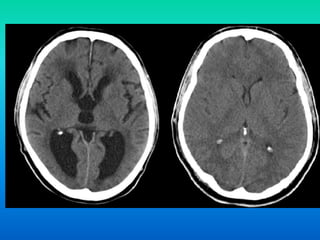

Cerebrovascular accident( CVA)- results in

destruction of neurons of the motor area of cerebrum

due to hemorrhage or cessation of blood flow through

cerebral blood vessels

-oxygen supply is disrupted and neurons die

- results in paralysis of opposite side of body where CVA

occurred (hemiplegia)

Cerebrovascular accident( CVA)-results in destruction of neurons of the motor area of cerebrum due to hemorrhage or cessation of blood flow through cerebral blood vessels -oxygen supply is disrupted and neurons die - results in paralysis of opposite side of body where CVA occurred (hemiplegia)